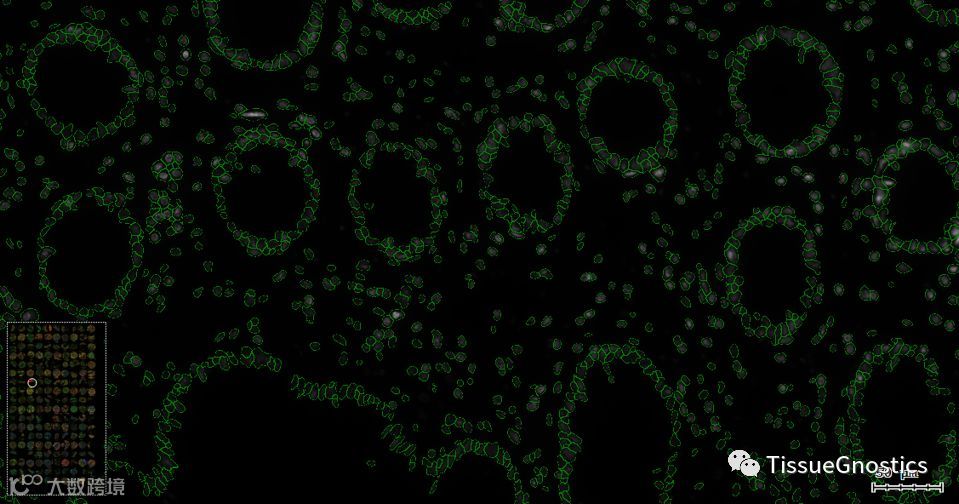

在光谱图像获取阶段,TissueFAXS系统通过对组织区域进行预览,根据每个TMA点的轮廓建立ROI区域后,对每个ROI区域影像进行获取。在分析阶段,TissueFAXS拥有的TMA重排功能,可以针对每一个ROI区域进行重排,获得可以实时缩放的、包含所有TMA点的全景影像。此功能解决了由于样本制备操作不当,导致的TMA芯片纵横距离差异问题,以获得更美观、更便于观察对比的图像信息。

原始影像(DAPI, 520, 540, 570, 620, 650, 690)

ROI区域内的TMA点的细节图像,支持影像无损缩放。

图中所示绿色标记是根据细胞核的形态进行识别后得到的细胞核轮廓。